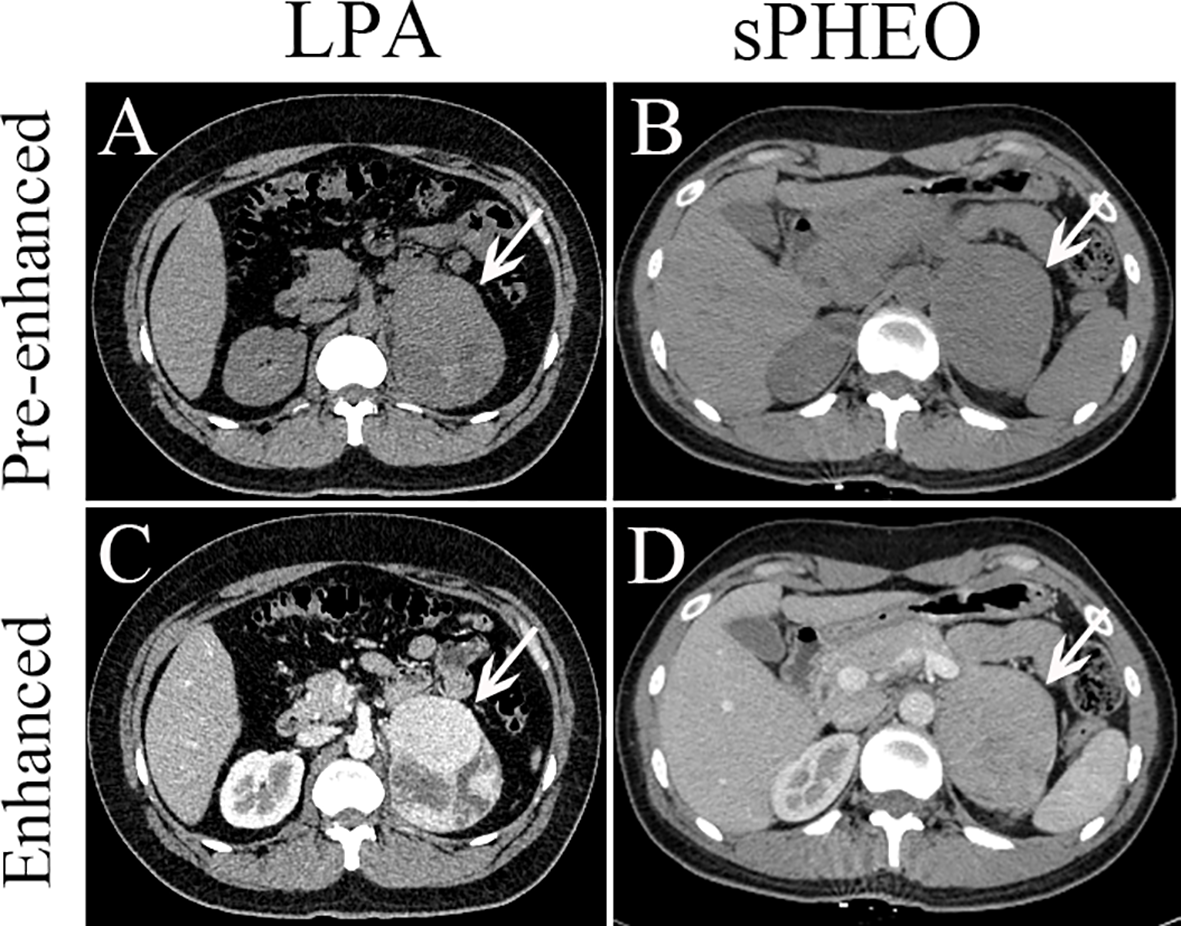

Comparison between patients with sPHEO and patients with LPA is presented in Table 1. A total of 269 patients were retrospectively included in this study. There were 92 tumors in 86 patients with sPHEO and 188 tumors in 183 patients with LPA. No significant differences were found in age, sex, and reasons for CT imaging between the two groups (all P > 0.05). Radiologically, many imaging features of sPHEO were overlapped with those of LPA lesions (Figure 2). The mean CT attenuation values for both pre-enhanced and enhanced CT of sPHEOs were significantly higher than those of LPAs (P < 0.01). In addition, sPHEOs were significantly larger than LPAs in both their long and short dimensions/diameters (P < 0.01).

Figure 2 Axial pre-enhanced and enhanced CT images of a patient with lipid-poor adenomas (LPA) (Case 95) and a patient with subclinical pheochromocytoma (sPHEO) (Case 21) showing left adrenal mass at the tumor largest dimensions. On pre-enhanced images, the LPA appeared as an irregular mass with intermediate heterogeneous density (A), while the sPHEO was an elliptical mass with relatively homogeneous density (B). After injection of contrast medium (65s), the LPA was markedly more heterogeneous, with obvious cystic and necrotic areas (C), while the sPHEO showed a mildly heterogeneous enhancement pattern (D).

There was no significant difference in distribution between the two tumor types. On pre-enhanced CT images, the 92 sPHEO tumors showed mildly to moderately heterogenous hyperattenuation, with mildly or intermediately heterogenous (n=66) or relatively homogenous (n=26) enhancement. On pre-enhanced images of the 188 LPA lesions, mild to moderate heterogeneity was found in 51 tumors and a homogenous pattern in 137 tumors. Following contrast-enhancement, mildly/markedly heterogenous (n=149) or homogenous (n=39) enhancement patterns were observed. On enhanced images, N/C imaging feature could be identified in 71.7% (66/92) of sPHEO masses and in 8.0% (15/188) of LPA lesions. Among the sPHEO lesions, 89 had a well-defined margin and the remaining three were ill-defined. Of the 188 LPAs lesions, only one had an ill-defined margin and the remaining 187 were all well-defined.